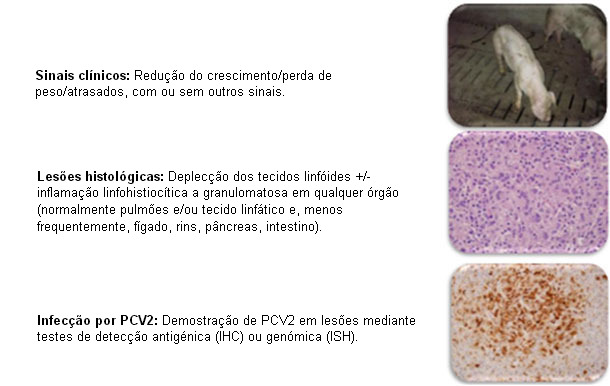

A incidência e o impacto da infecção por Circovirus Suíno Tipo 2 (PCV2) e as suas patologias associadas (PCVAD, antigamente PMWS) modificaram-se consideravelmente nos últimos 15-20 anos. Antes de 2004, o PCV2 tinha uma elevada prevalência na população suinícola mas costumava ser assintomático, pelo que não havia muita confiança no diagnóstico das doenças associadas a este agente. A definição clínica e os critérios diagnósticos do Sindroma da falta de crescimento multisistémico pós-desmame (PMWS, actualmente PCVAD) foram recolhidos por Sorden no ano 2000 (figura 1) e foram amplamente aceites pela comunidade veterinária já que a doença se propagou por todo o mundo, podendo corroborá-los na prática. Sorden incorporou, sabiamente, os sinais clínicos típicos, as lesões típicas e a demostração do vírus na definição clínica e nos critérios diagnósticos.

Figura 1: PMWS: Definição clínica. Sorden, Swine Health Prod 8(3):133-136, 2000

O diagnóstico de um porco ou grupo de porcos requer: